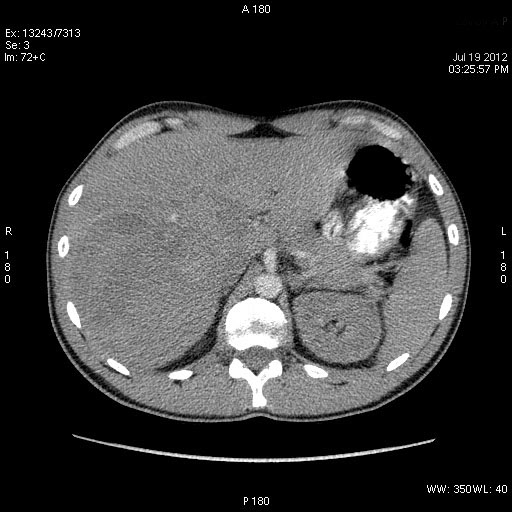

На следующий день сонографическая картина немного изменилась:

Какие мысли?

на узи на абсцесс не похоже, образование солидное ----гепатома?

Гигантская капилярная гемангиома печени.

1. Это абсцесс или опухоль?

2. Если опухоль, то доброкачественная она или нет?

Ультразвуковаое контрастирование может помочь в этом.